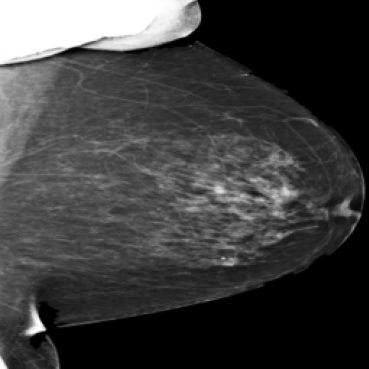

The 136 true outliers are classified into seven categories by the professional radiologist: implant, pacemaker, cardiac loop recorder, improper radiography, atypical lesion/calcification, incorrect exposure parameter and improper placement. It is worth noting that, despite the fact that mammograms with implants were eliminated during the preprocessing step (see Section 2.6), there were still mammograms with implants remaining since they were incorrectly categorised as having no implants. Figure 1 depicts representative outliers for each category, and Table. 4 displays the number and percentage of outliers in each category given that that the total number of true outliers is 136.

Figure 1: Examples of true outlier subgroups in the ADMANI dataset. From left to right and top to bottom, the outlier types are: implant, pacemaker, cardiac loop recorder, improper radiography, improper radiography, atypical lesions/calcification, incorrect exposure parameter, improper placement. Improper radiography is classified into two subtypes: those with heterogeneous pectoral muscle and the rest, respectively.